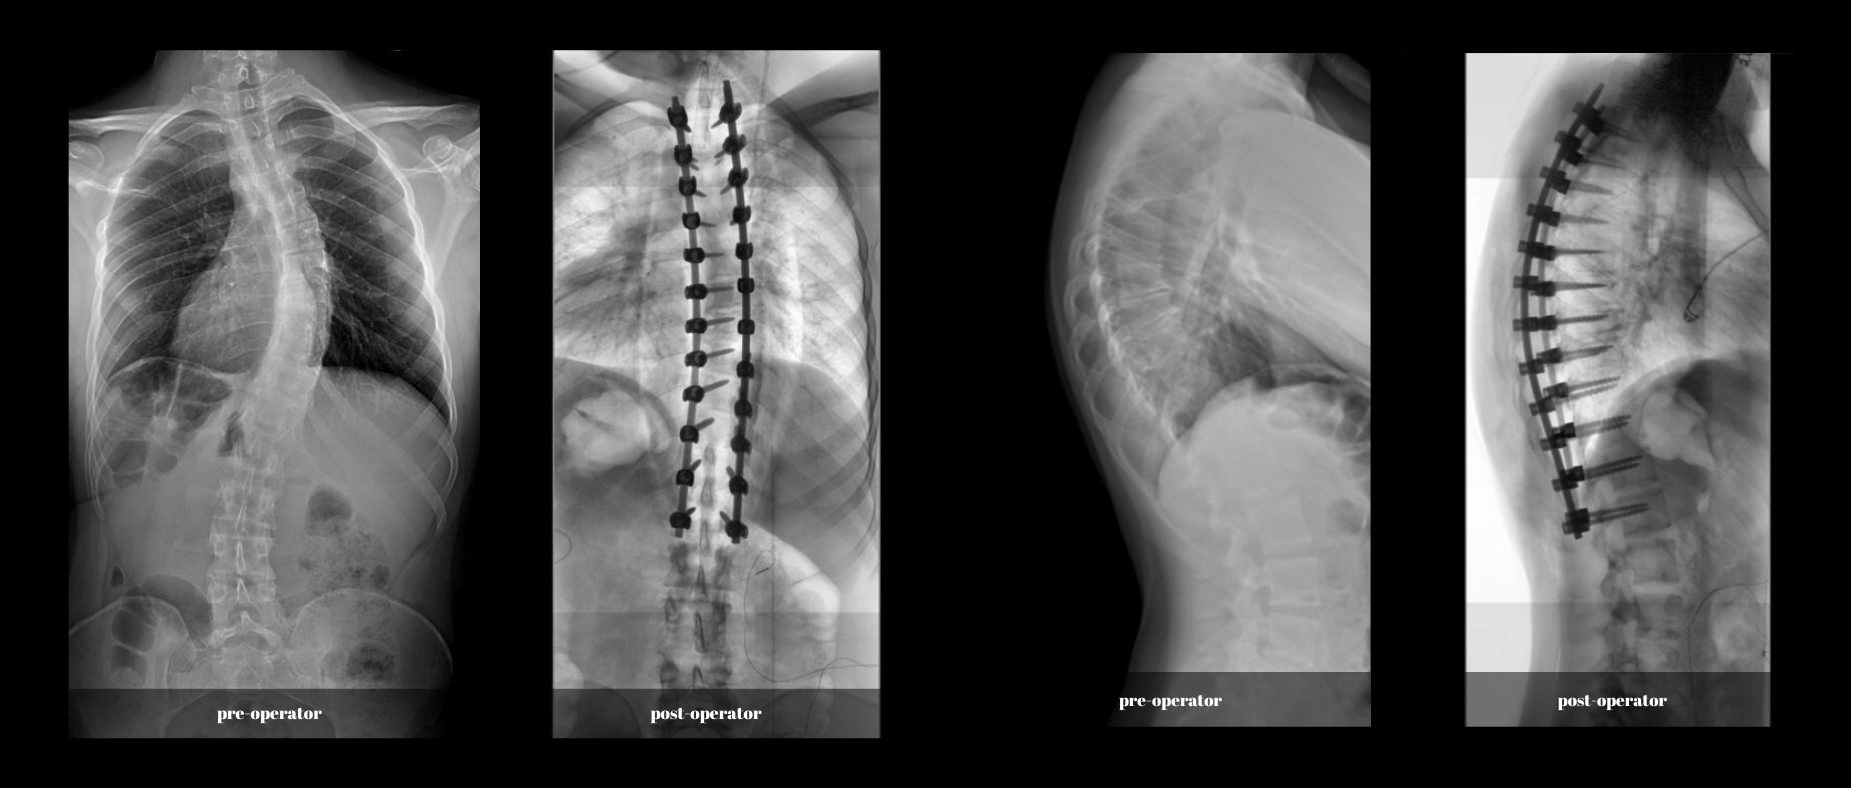

După o evaluare amănunțită și un plan de tratament personalizat, tânărul a ales să se supună unei intervenții chirurgicale la BRAIN Institute, sub îngrijirea dr. Mihai Sabin Măgurean și dr. Alexandru Thiery de la Spitalul Monza. Echipa de experți a folosit cele mai avansate tehnologii disponibile, inclusiv robotul chirurgical Mazor X cu sistem de navigație tip Stealth și neuromonitorizare continuă intraoperatorie.

După o intervenție chirurgicală de succes care a durat 8 ore, tânărul se bucură acum de o recuperare în curs și de perspective promițătoare pentru viitor. Încrederea în echipa medicală și în tehnologiile moderne i-au readus speranța la o viață normală și activă.